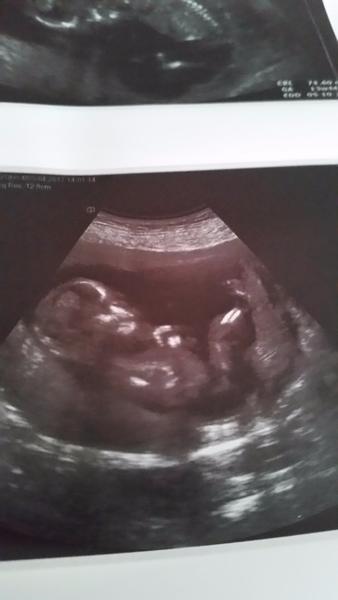

moc pekne vam dakujem baby a ako inspiraciu aby ste to nezvladali prikladam foto snad nikoho sa tym nedotnem

@vanda12345 uvedomujes si, kolko pozitivnej energie dokaze taka fotka dat? 🙂 krasna 😘

@vanda12345 ako si t6m pekne lezka,ako v postielke🙂

@kakatulik total pohoda nohy vylozene lekarka vravela ze viac sedi ako lezi aj inak nam pozovala uzasne to bolo❤